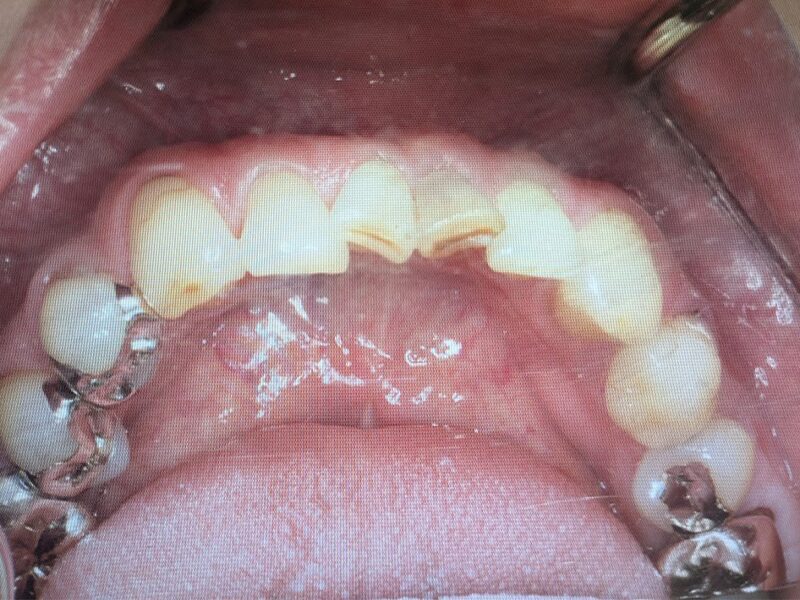

根管治療を行い、歯肉の膿瘍が消失しています。手術の準備が整いましたので手術を実施いたします。

術後3か月です。